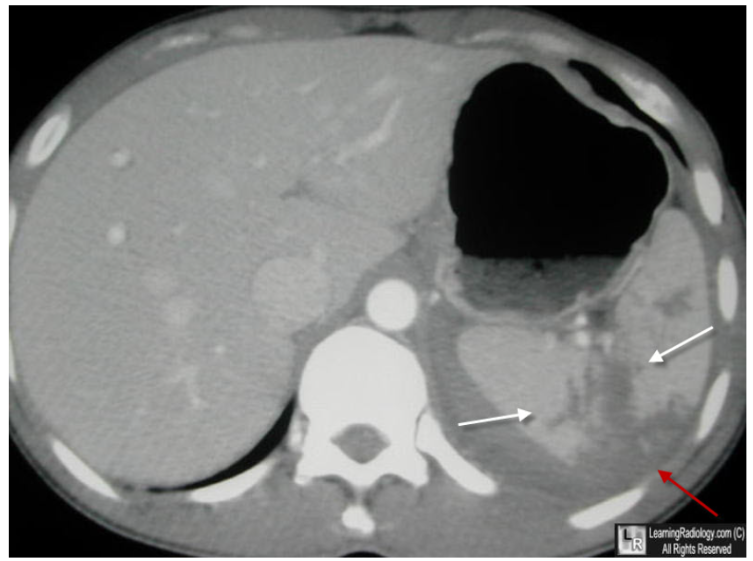

1. High-grade splenic injury/devascularization (AAST grade IV-V) with large volume hemoperitoneum. No evidence of active extravasation or pseudoaneurysm.

2. Hyperattenuating adrenal glands and mild flattening of the IVC, which can be seen in the setting of CT hypoperfusion complex.

3. No pneumoperitoneum or acute osseous abnormality.